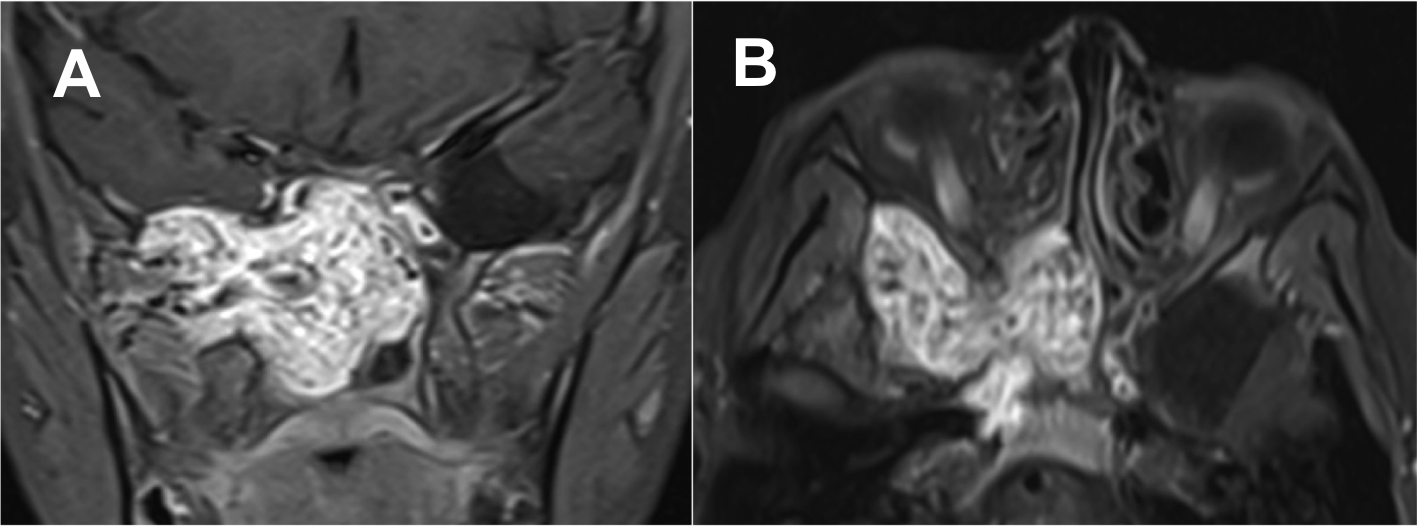

Introducción: La cirugía endoscópica endonasal se ha convertido en una herramienta fundamental para el manejo de patologías que comprometen la base de cráneo. En casos bien seleccionados, estas técnicas permiten resecciones quirúrgicas con una menor morbilidad sin comprometer los principios oncológicos de resección. Con el desarrollo de instrumental especializado, nuevas tecnologías y la experiencia de los cirujanos, la cirugía endoscópica endonasal se usa cada vez más en cirugía de base de cráneo en niños.

Objetivo: presentar una serie de casos de pacientes pediátricos con tumores de base de cráneo manejados con cirugía endoscópica endonasal.

Diseño: Estudio observacional descriptivo de tipo serie de casos. Metodología: se describe la experiencia con pacientes pediátricos llevados a cirugía endoscópica endonasal para manejo de tumores de base de cráneo en el Instituto Nacional de Cancerología entre julio de 2014 y diciembre de 2016.

Resultados: Fueron intervenidos 8 pacientes entre los 2 y 14 años, con una edad promedio de nueve años y un seguimiento promedio de 16 meses. En el 75% se hizo una resección total del tumor. Un paciente requirió una reintervención y un paciente fue sometido a radiocirugía post-operatoria. 1 paciente falleció a pesar de múltiples intervenciones, quimioterapia y radioterapia.

Conclusión: La cirugía endoscópica endonasal para tumores de base de cráneo puede ser utilizada de forma segura en los pacientes pediátricos, es una técnica que en casos bien seleccionados pueden ofrecer excelentes resultados disminuyendo la morbilidad y complicaciones de las técnicas abiertas.